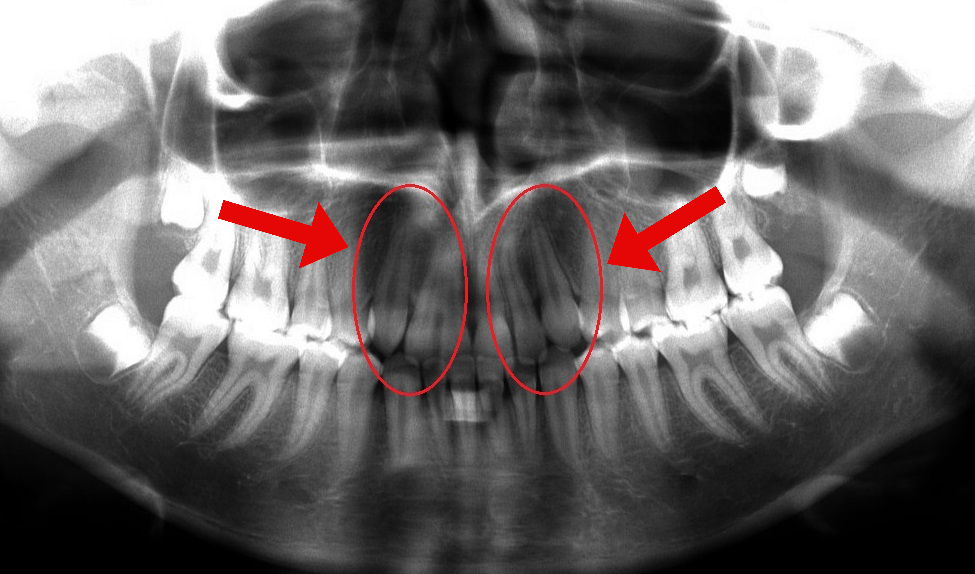

Caso 2

Esta paciente acudió a consulta porque uno de sus dientes frontales de leche no se había caído. Una radiografía panorámica mostró que su diente frontal permanente estaba impactado y atrapado en una posición alta dentro del maxilar, como se observa en la primera fotografía.

Aunque inicialmente se recomendó la extracción, optamos por una alternativa más conservadora. Mediante la colocación de un pequeño dispositivo de ortodoncia, pudimos guiar suavemente el diente hasta su posición correcta. Este enfoque permitió conservar su diente frontal natural y evitó la necesidad de un implante, algo que nunca puede reemplazar por completo una sonrisa natural.